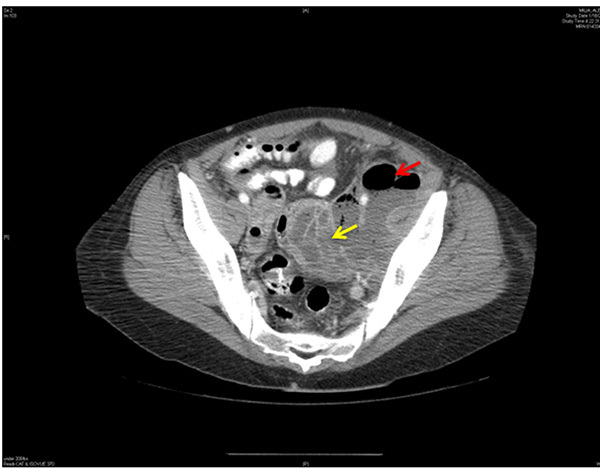

When TOA is suspected, imaging to rule out the condition should be performed promptly. On both ultrasound and contrast-enhanced CT imaging, TOA manifests as a complex fluid collection with internal septations. (See Figures 1 and 2.) Surrounding nonspecific inflammatory changes likely will be seen, such as fat stranding on CT scan and free fluid in the cul-de-sac. Air within the structure is less common but may be present. The differential diagnosis for these findings includes a complex ovarian neoplasm, and the clinician should use systemic findings to help differentiate the two.26

Figure 2. CT Scan of the Pelvis Shows a Large Loculated Abscess with Air in the Left Pelvis |

Loculated abscess indicated by yellow arrow. Air is shown by red arrow. CT: computed tomography Image courtesy of Basil Hubbi, MD, Department of Radiology, Rutgers New Jersey Medical School. |